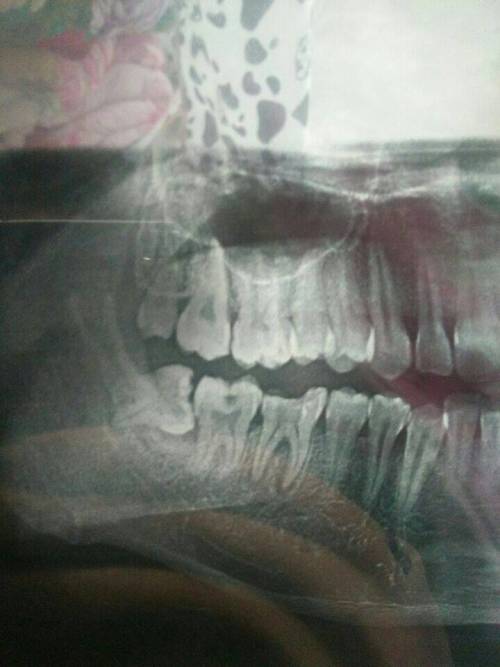

1、術(shù)前檢查:拔智齒前需要進(jìn)行口腔檢查、X光片等檢查,以了解智齒的位置和周圍結(jié)構(gòu),這些檢查費(fèi)用也是拔智齒總費(fèi)用的一部分。